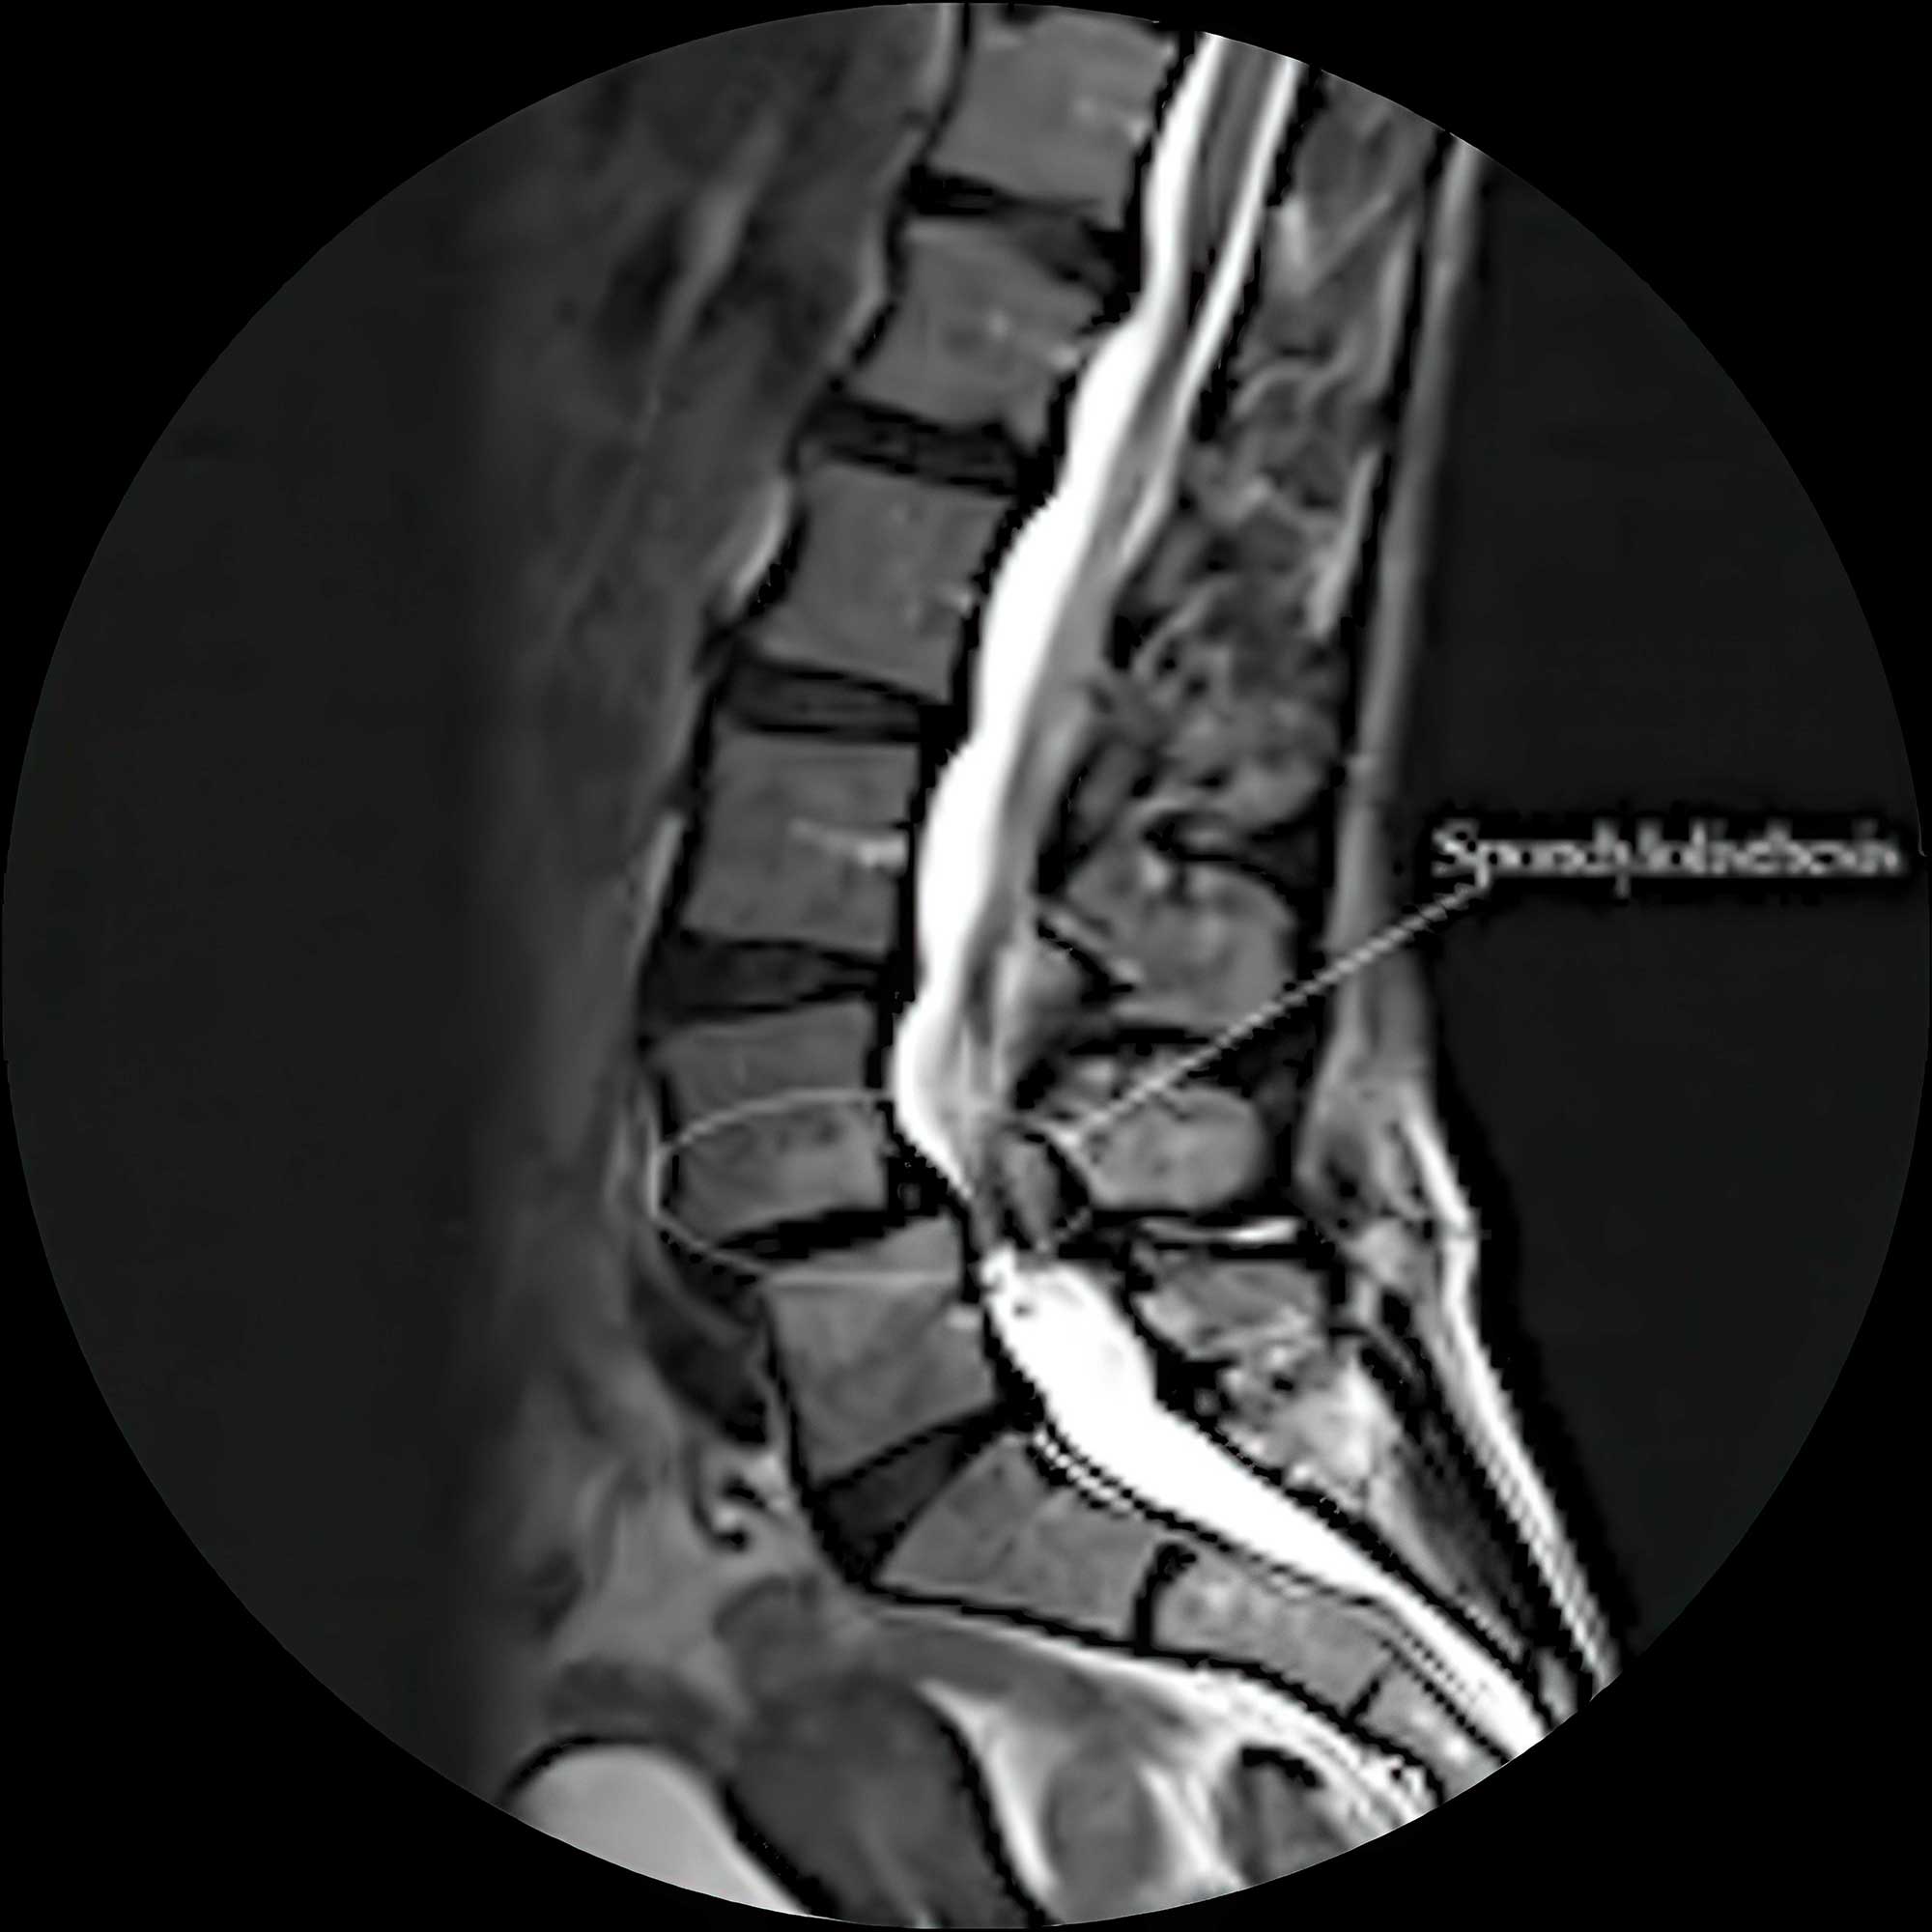

L4/L5 spondylolisthesis

Unstable spine requiring surgical correction.